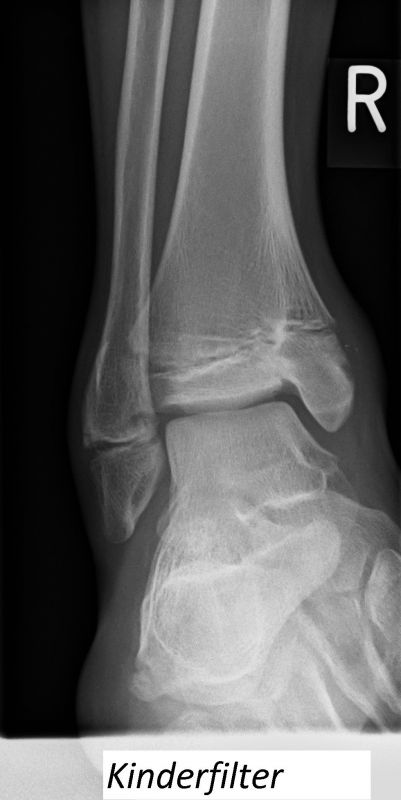

Fugengelenkfrakturen treten typischerweise vor dem 10. Lebensjahr auf, in einer Phase, in welcher die Wachstumsfugen noch weit offen sind. Dieser Frakturtyp betrifft fast ausschließlich den medialen Malleolus. Laterale Frakturen sind extrem selten, teilweise kommt es zu lateralen Bandverletzungen oder Fugenschaftfrakturen der distalen Fibula. Die Frakturlinie verläuft in einer Verlängerungslinie von der medialen Taluskante nach proximal. Häufig stellen sich Verletzungen des Innenknöchels im Röntgenbild schlechter dar, insbesondere wenn die Aufnahmen verdreht sind oder die Ebene der Fraktur bei geringer Dislokation verkippt zur Röntgenebene liegt. Besteht klinisch der geringste Hinweis auf eine Verletzung des Innenknöchels, muss aufgrund der Tragweite der Verletzung durch entsprechende Aufnahmen gegebenenfalls auch Schnittbildverfahren die Verletzung sicher diagnostiziert oder ausgeschlossen werden (Abb. 15).

„Kadiläsion“- Mediale Malleolarfraktur

Bei kindlichen Verletzungen des medialen Malleolus handelt es sich nach L. v. Laer um eine sogenannte Kadiläsion, d.h. eine Verletzung mit hohem Risiko eines schlechten Behandlungsergebnisses bei nicht korrekter Behandlung. Selbst bei optimaler Therapie ist das Risiko für spätere Wachstumsstörungen hoch, sodass diese Verletzungen nicht selten ein juristisches Nachspiel haben. Durch die Verletzung der wachstumsaktiven Zone kann es zu einem vorzeitigen Verschluss der Wachstumsfuge kommen, mit entsprechendem Fehlwachstum. Das Risiko eines vorzeitigen Verschlusses der Wachstumsfuge korreliert mit dem Ausmaß der Schädigung der wachstumsaktiven Zone. Ab dem 13. Lebensjahr wird das Risiko bei reduzierter Wachstumsaktivität zunehmend geringer.

Fugengelenkfrakturen können die Wachstumsfuge durchkreuzen (Abbildung 16a), ohne oder nur mit minimaler Beteiligung der Fuge sehr weit medial liegen (Abbildung 16b) oder durch die Fuge auslaufen (Abbildung 16c). Relevant für die Wachstumsprognose ist weniger die Form der Fraktur, sondern das Alter des Patienten zum Zeitpunkt des Traumas sowie das Ausmaß der Schädigung der Wachstumsfuge, wobei eine Korrelation mit dem Ausmaß der Dislokation besteht.